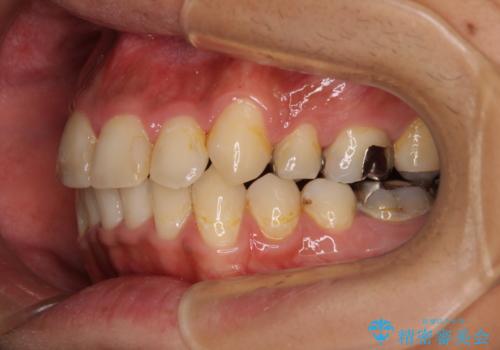

八重歯と開咬 ワイヤー装置での抜歯矯正

- 前歯のデコボコと八重歯、開咬を気にして来院された患者様です。

骨格的に下顎骨が上顎骨に対して後退位であったため、上顎の左右第一小臼歯を抜歯し、デコボコを改善するとともに開咬を改善していくこととしました。

舌の突出癖により開咬となっていたため、突出癖改善のためのトレーニングをしっかりと行っていただき、予定の期間で無事に治療を終えることができました。